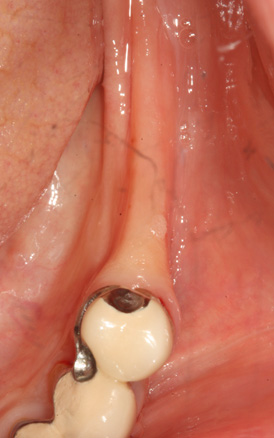

상악동 거상술

상악동 거상술 고난이도 뼈이식술 입니다.

청담네오플란트에서는 상악동 거상술을 비롯한

고난이도 임플란트 시술 노하우가 풍부한 치의학 박사

전문의가 직접 상악동 거상술을 시행합니다

상악동은 윗턱뼈 내부의 구조물로서 개개인에 따라 생김새가 다릅니다.

상악동의 바닥이 잇몸뼈 방향으로 많이 내려온 경우, 임플란트를 식립하기에

잇몸뼈가 부족하게 됩니다. 이러한 경우 상악동 내부로 뼈이식을 하는

상악동 거상술이 필요하게 됩니다.

B

A